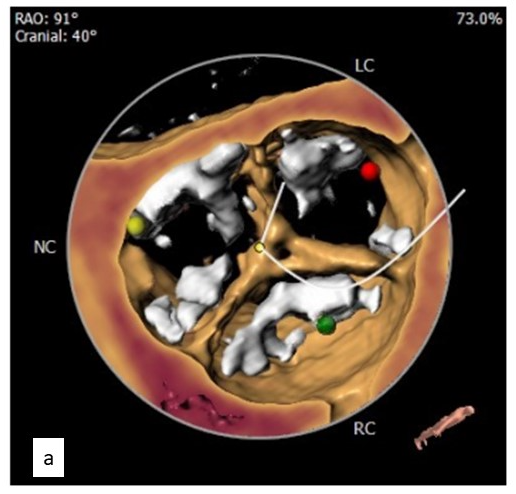

With a Euro SCORE II of 12%, the patient was deemed a high-risk surgical candidate and was prepared for TAVR. Computerized tomography for TAVR evaluation showed a calcified tricuspid aortic valve (Figure 1a) with a mean aortic annulus of 23.1 mm, mean left ventricular outflow tract diameter of 22.3 mm, left coronary height of 14 mm, and right coronary height of 18.6 mm. The patient had bilateral diffuse lower-limb atherosclerosis.

There was no coronary obstruction, and the patient was hemodynamically stable. Using a bioptome (Cordis), the valve was pulled high in the aorta, leaving it just proximal to the origin of the brachiocephalic artery (Figure 4). The aortic valve was recrossed and another 26-mm Evolut R self-expanding valve was deployed successfully (Figure 5).